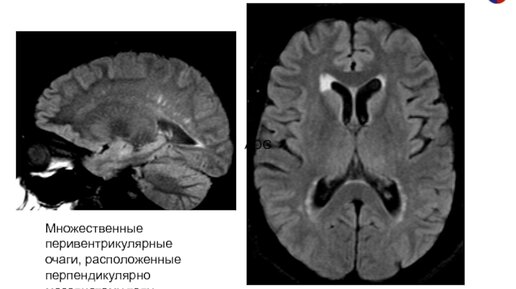

Дисциркуляторная энцефалопатия или ДЭ

Дисциркуляторная энцефалопатия: что это такое и как ее предотвратить? Дисциркуляторная энцефалопатия (ДЭ) - это заболевание, которое связано с нарушением кровоснабжения мозга и может привести к различным неврологическим и психическим расстройствам. Она часто возникает у пожилых людей, но может проявляться и у молодых людей. При ДЭ мозг не получает достаточно кислорода и питательных веществ, что приводит к постепенному ухудшению его функций. Симптомы ДЭ могут быть различными и включают в себя головокружение,...